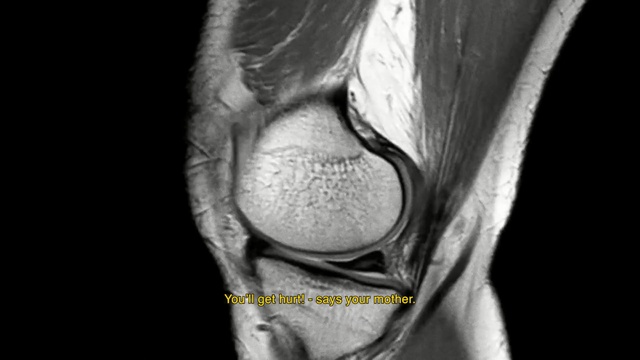

Best Video References: Knee pain

Featured videos selected by a smart neural network algorithm